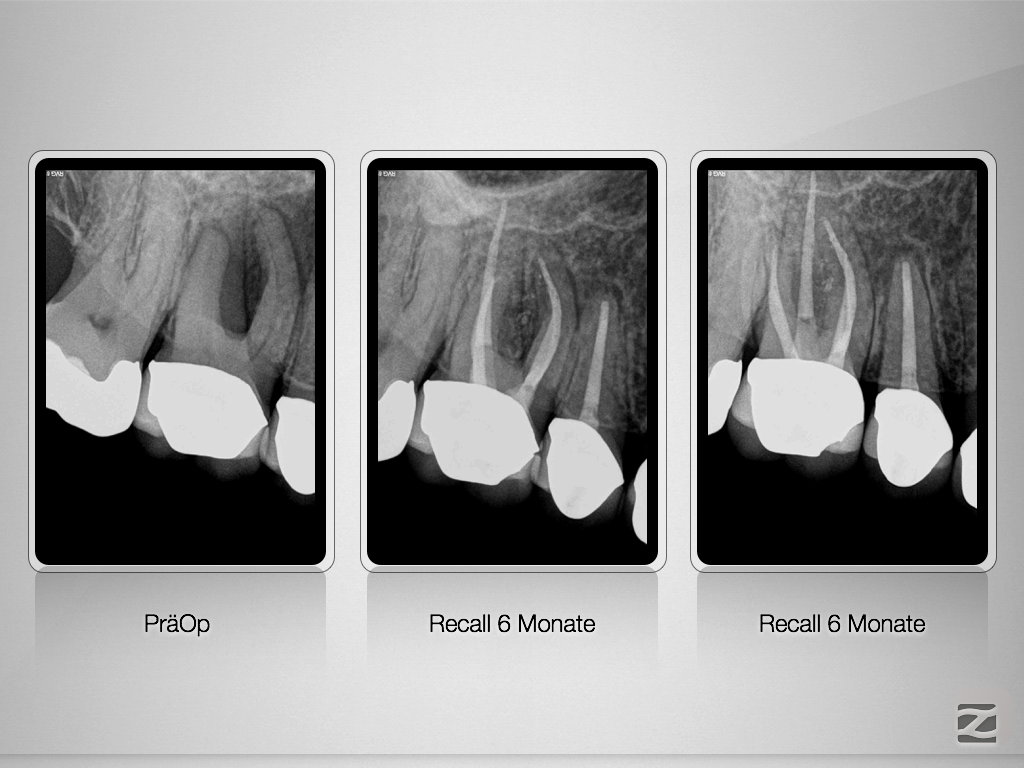

Endo-Paro-Läsion